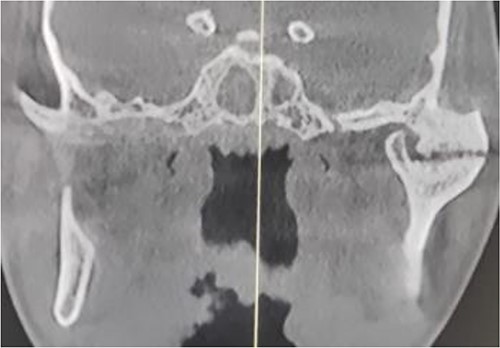

The clinical examination of the patient revealed a bird face deformity, chin deviated to the right side, restricted mouth opening of about 5 mm (Fig. 2), class II malocclusion on the right side and class I malocclusion on the left side with protruding upper anterior teeth and an open anterior bite. Cone-beam computed tomography images showed left-sided bony ankylosis of the temporomandibular joint (Fig. 3). Since the patient is skeletally mature, mandibular growth is ceased, and there is recurrent TMJA, reconstruction with an artificial prosthesis can be used as an alternative option [9, 10]. In this case, resection of the left-sided ankylotic bony mass with reshaping of the remaining bilateral ramus and temporal bone was performed for fitting and fixation of a custom made temporomandibular joint prosthesis of Lyka Smith (Fig. 7), Williams Landing, Australia, followed by advancement genioplasty (Figs 8 and 9) [10].

Preoperative computed tomography (coronal section): left-sided TMJA with radiographic suggestion of previous condylectomy at right-sided temporomandibular joint.